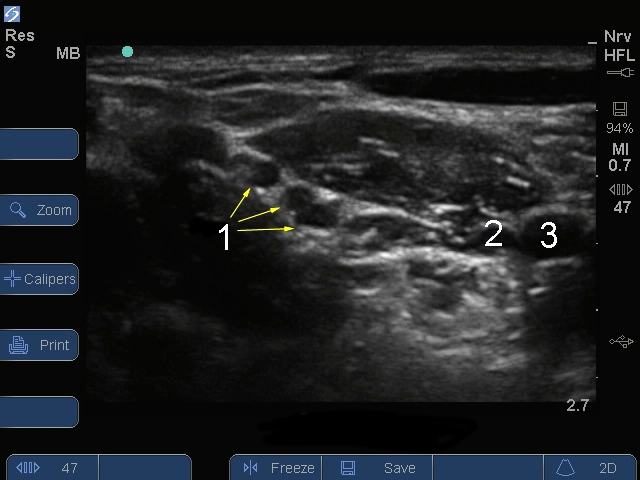

Sシリーズ:腕神経叢斜角筋間レベル1画像

神経

静脈

動脈